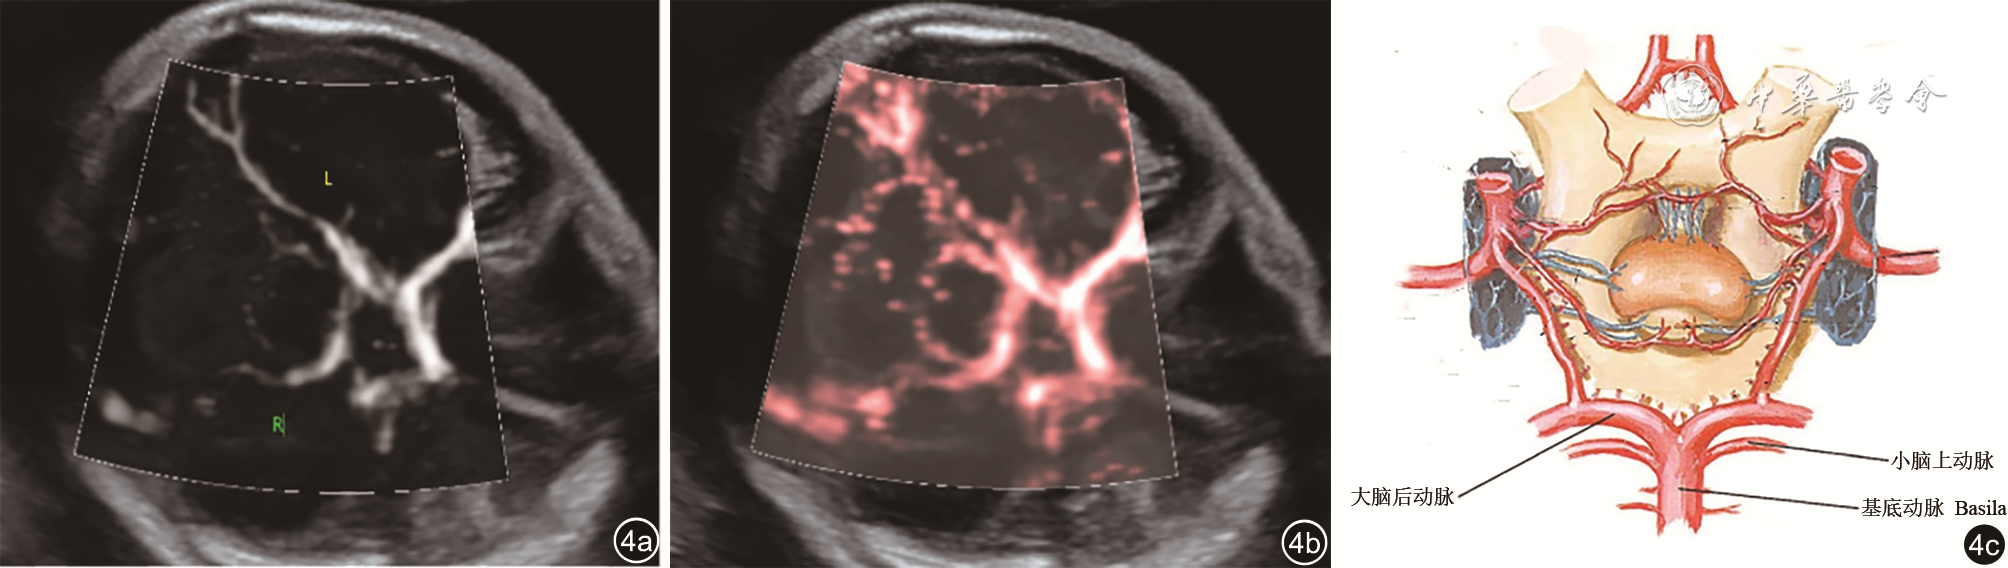

2. 微血流显像检查2例,发育不全侧小脑上动脉均不显示,对侧小脑上动脉可显示(图45)。

图4 正常胎儿小脑上动脉血供超声声像图(图a、b)及小脑上动脉走行模式图(图c),显示小脑上动脉起自基底动脉并与大脑后动脉伴行(图片引自《奈特人体解剖学彩色图谱第6版》)

此外,超声还可在一定程度上观察到小脑半球的血供情况。Leibovitz等16通过后颅窝高分辨率多普勒超声观察了7例UCH胎儿,显示部分胎儿存在小脑供血动脉异常如小脑下后动脉缺失等。本院产前诊断的6例UCH胎儿中2例亦通过产前超声Micro F显微血流技术显示出双侧小脑半球血流不对称,一侧大脑后动脉及小脑上动脉走行可清晰显示,而发育不全侧仅显示大脑后动脉,小脑上动脉血流不显示。

微血流显像是一种新的超声血管成像技术,具有高灵敏度、高分辨率检测低速血流的特点,相较于彩色多普勒,微血流显像更易检出血流速度较低的微血管19,既往多运用于甲状腺、乳腺、肝等肿瘤疾病的诊断。现首次将微血流显像技术用于观察胎儿小脑的血管,从解剖角度看,小脑上动脉起自基底动脉,沿着小脑与脑干之间由后外向内前行的过程中逐渐发出小脑支和脑干支并布于小脑上面和中脑、脑桥背面20,而大脑后动脉与小脑上动脉伴行且呈平行走向,绕大脑脚向后走行。在小脑横切面微血流显像中,大脑后动脉和小脑上动脉显示呈平行走向的关系,因此,通过大脑后动脉可以判断小脑上动脉的位置及缺失与否,起到一定的辅助诊断作用。但此方法的不足在于目前仅通过小脑横切面对小脑幕面的小脑上动脉显示,其余小脑动脉的显示情况有待进一步研究。